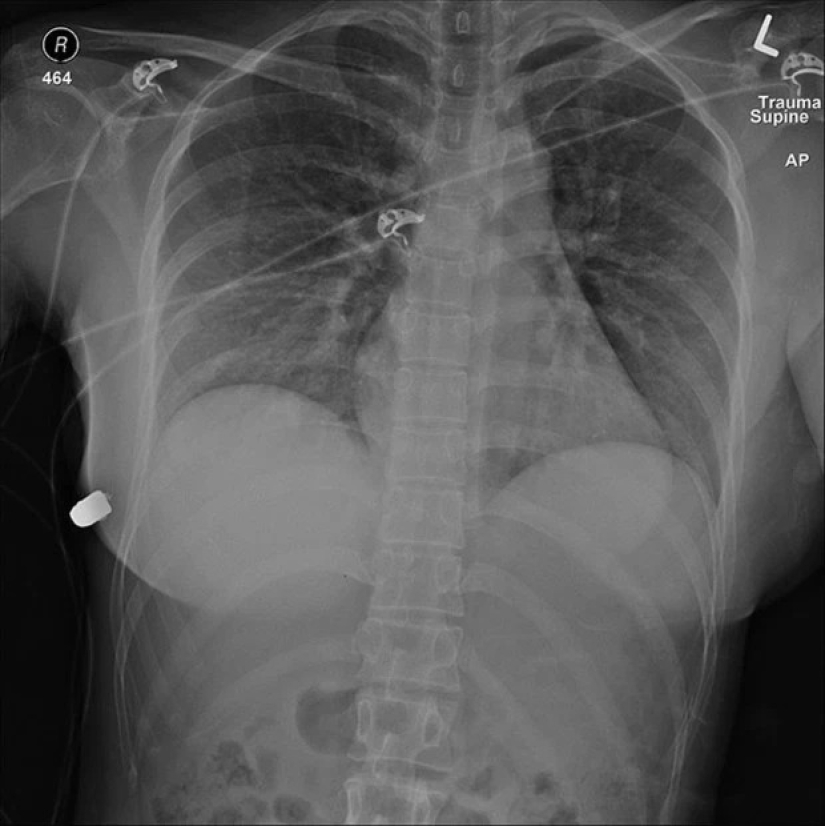

Sheila Hershey tenía un pecho impresionante de enorme tamaño, gracias al cual se hizo famosa en el mundo de la moda. El busto de silicona trajo a la anfitriona no solo fama, sino que también le salvó la vida en un accidente automovilístico, trabajando como una bolsa de aire.

El coche de la modelo de 40 años se estrelló contra un árbol a gran velocidad mientras conducía a casa por la noche. Toda la vida de la mujer pasó ante sus ojos. Los impresionantes implantes suavizaron el golpe y salvaron la vida de Sheila. El pecho de la bella estaba dañado, pero el resto de su cuerpo permaneció intacto.